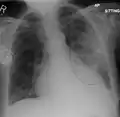

Normal AP CXR

Normal lateral CXR